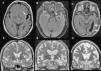

La afasia es una alteración adquirida del lenguaje debida a una lesión cerebral, que se caracteriza por errores en la producción, la denominación o la comprensión del lenguaje. Aunque la mayoría de las afasias suelen ser mixtas, desde un punto de vista práctico se clasifican en diferentes tipos según sus rasgos clínicos principales: afasia de Broca, afasia de Wernicke, afasia de conducción, afasia transcortical y alexia con o sin agrafia. Presentamos los hallazgos clínicos de los principales subtipos representándolos con casos radiológicos, y proporcionamos una revisión actualizada de la red del lenguaje con imágenes de resonancia funcional y de tractografía.

Aphasia is an acquired language disorder due to a cerebral lesion; it is characterized by errors in production, denomination, or comprehension of language. Although most aphasias are mixed, from a practical point of view they are classified into different types according to their main clinical features: Broca's aphasia, Wernicke's aphasia, conduction aphasia, transcortical aphasia, and alexia with or without agraphia. We present the clinical findings for the main subtypes of aphasia, illustrating them with imaging cases, and we provide an up-to-date review of the language network with images from functional magnetic resonance imaging and tractography.